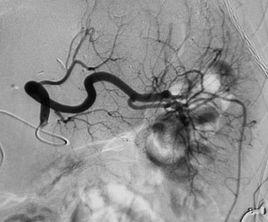

(五)螺圈(coil)

也稱不鏽鋼圈、彈簧圈,為機械性栓子,可用於大、中小動脈,永久閉塞血管,對機體無活性作用。